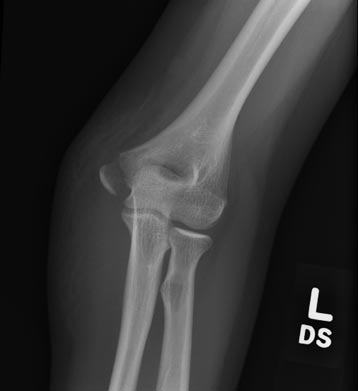

Before Surgery

Non-Union of Distal Humerus Elbow Fracture

Displaced Condyle Fracture